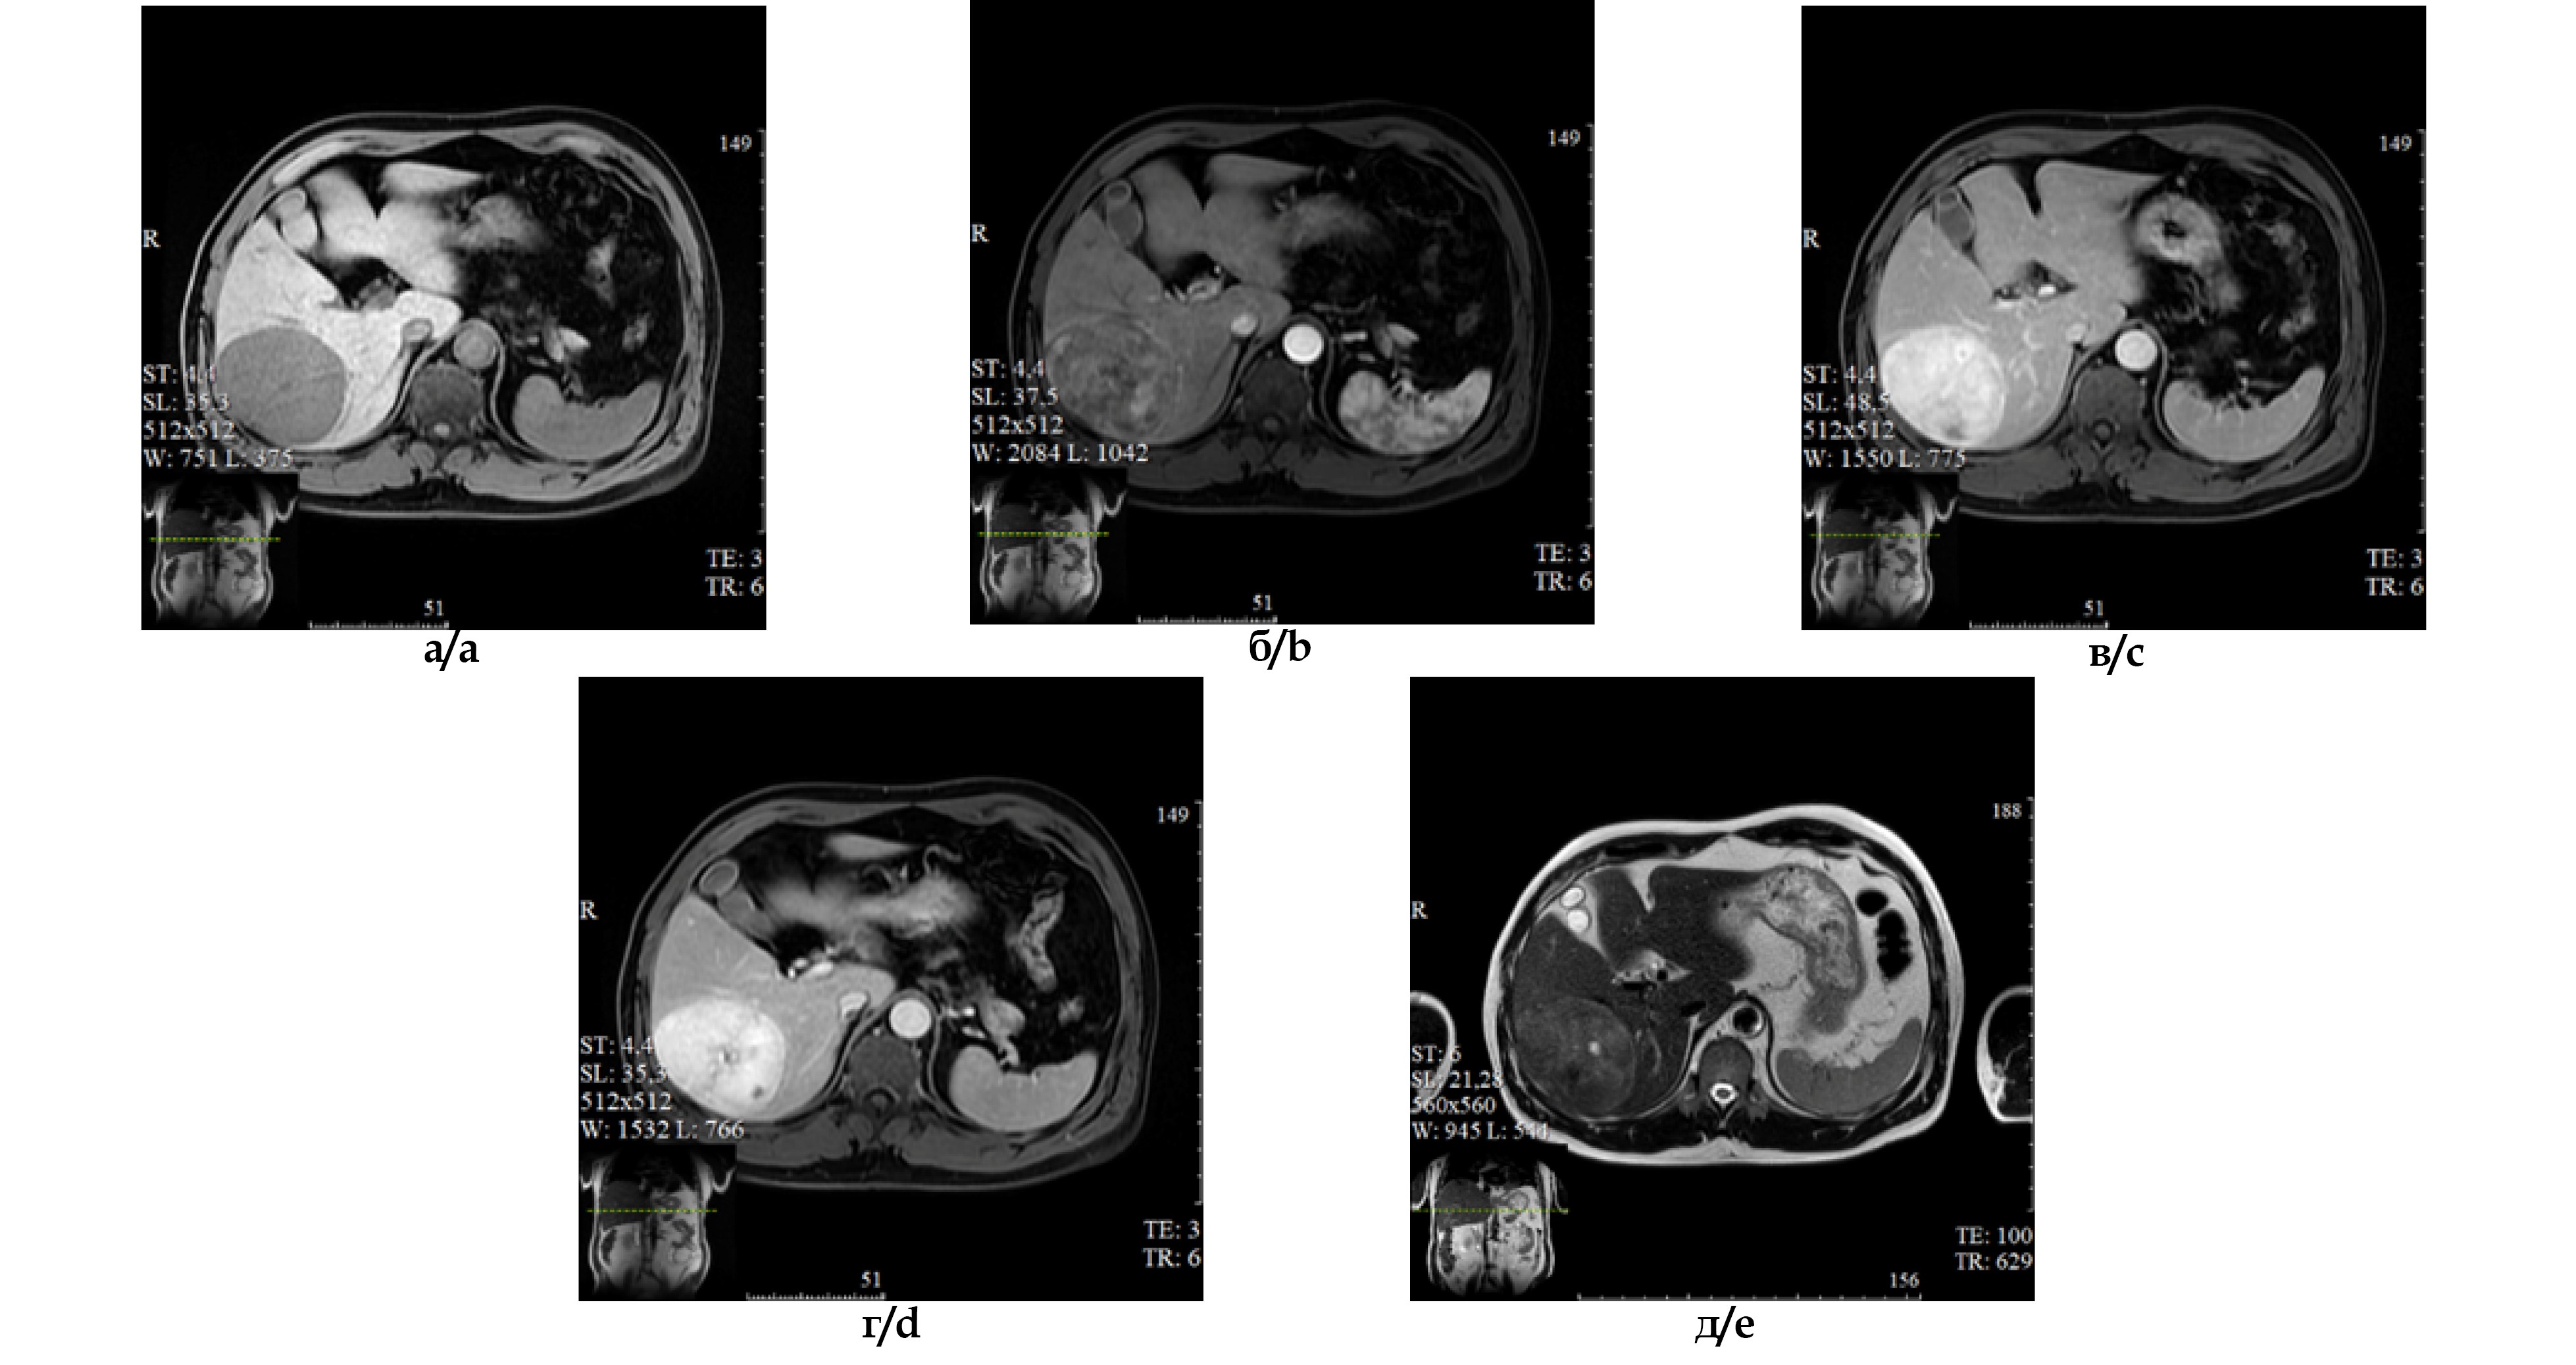

Магнитно-резонансная томография. В VI, VII сегментах печени определяется округлое образование с четкими ровными контурами неоднородной структуры, размерами 89х70 мм, в центре определяются участки некроза (рис. 2а). При контрастировании (рис. 2 б-г) отмечается неоднородное выраженное контрастирование в артериальную фазу (рис. 2б), максимальное накопление КС отмечается в паренхиматозную. В центре образования гиперинтенсивные на Т2ВИ участки (вероятно, участки некроза) (рис. 2д).

Рис. 2. МРТ-изображения органов брюшной полости с внутривенным болюсным контрастированием (гедоксетовой кислотой); а – нативная фаза, б – артериальная фаза, в – венозная фаза г – отсроченная фаза, д – Т2-взвешенное изображение.

Fig. 2. Enhanced (Gadoxetic acid) MRI of the abdomen: a – unenhanced phase; b – arterial phase; c – venous phase; d – delayed phase; e - T2WI.

Магнитно-резонансная томография (оценка динамики через три месяца). В VI, VII сегментах печени определяется округлое образование с четкими ровными контурами, неоднородной структуры, размерами 92х101 мм (увеличение размеров при сравнении с данными предыдущего исследованиям). В центре образования гиперинтенсивные на Т2ВИ участки (вероятно, участки некроза). На DWI в структуре солидного компонента образования отмечается умеренное ограничение диффузии (рис. 4а), ИКД несколько снижен в солидных участках новообразования (рис. 4б). Признаков инвазивного роста образования нет. Других образований в структуре печени не определяется.

Рис. 4. Результаты МРТ в режимах DWI (а) и ИКД (б).

Fig. 4. MRI in DWI (a) and ADC (b).

ЛУ в воротах печени, а также парааортальные не изменены. Патологических изменений в желчевыводящей системе, поджелудочной железе и селезёнке не выявлено.

Заключение. Образование правой доли печени, наиболее вероятно гепатоцеллюлярный рак (воспалительная псевдоопухоль?), увеличение размеров при сравнении с предыдущим исследованием.